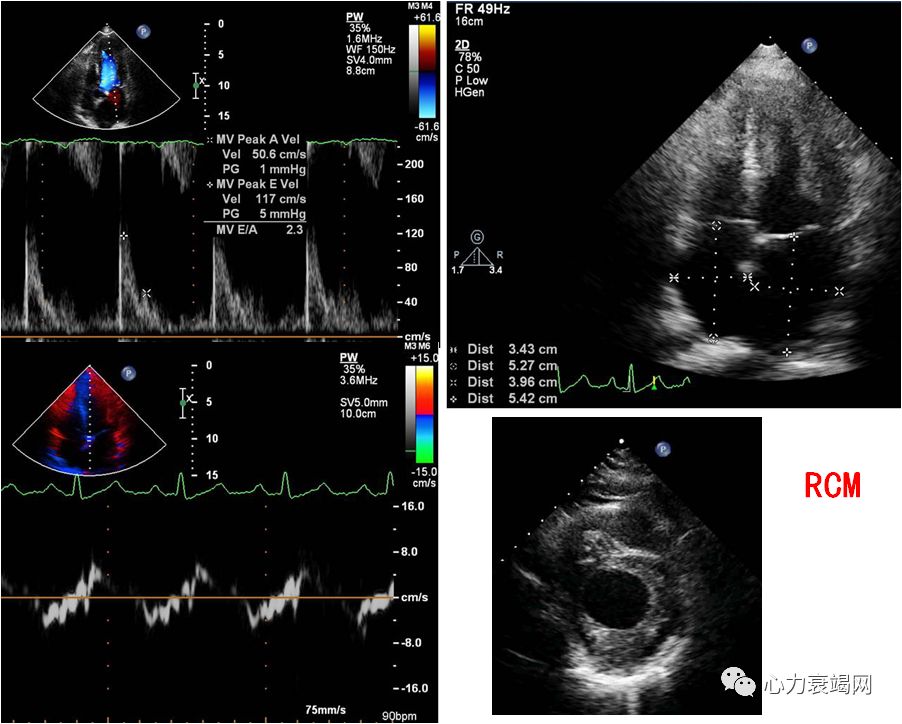

➤ 典型的CSS分病程初始常为哮喘、过敏性鼻炎,此后出现心内膜心肌的嗜酸性粒细胞浸润。

引起类似Loftier心内膜炎的心脏病变。

心室心尖闭塞及限制性心肌病,心腔内血栓形成,心内膜和心肌间质纤维化。

➤ 部分患者并不出现典型的Loftier心内膜炎的改变,而主要表现为坏死性心肌血管炎导致的心脏扩大、心力衰竭或心律失常。

心衰患者心内膜广泛增厚或血栓形成常是高嗜酸细胞血症(包括CSS)累及心脏。